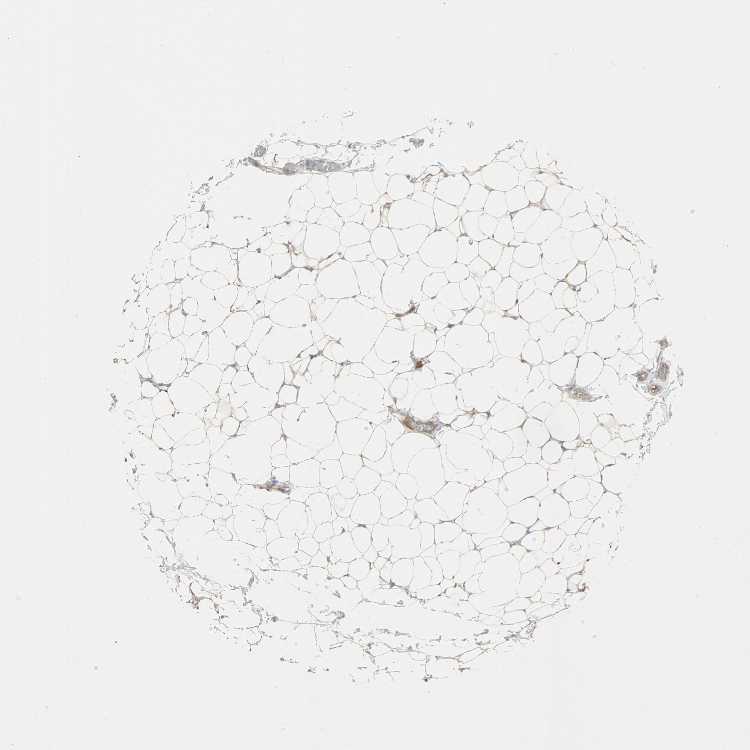

ADIPOSE TISSUE - Antibody stainingi

Antibody staining in the annotated cell types in the current human tissue is reported as not detected, low, medium, or high, based on conventional immunohistochemistry profiling in selected tissues. This score is based on the combination of the staining intensity and fraction of stained cells.

Each image is clickable and will lead to virtual microscopy that enables deeper exploration of all samples and also displays staining intensity scores, fraction scores and subcellular localization as well as patient and tissue information for each sample.

Antibody HPA005726

Adipocytes Not detected